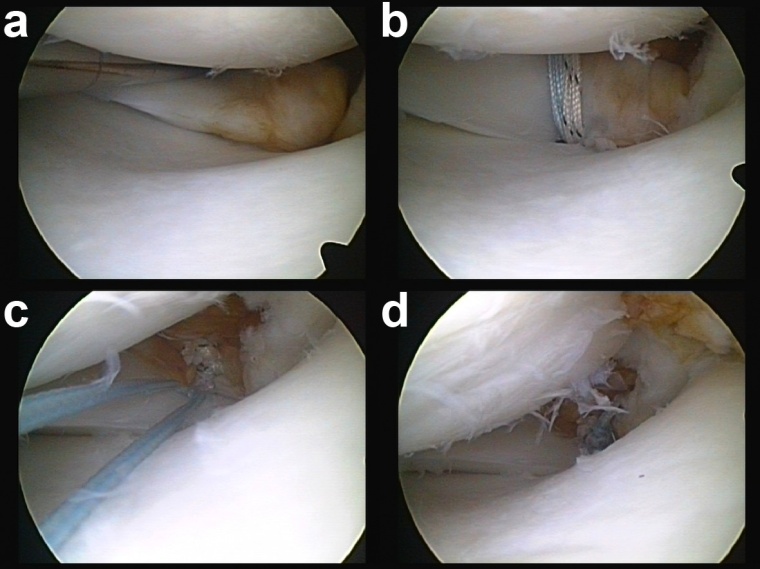

Aufgrund der schwerwiegenden Folgen dieser Verletzung und den nur unbefriedigenden Ergebnissen nach konservativer Therapie oder Meniskus-Teilresektion wird mittlerweile die arthroskopische Refixation der Meniskuswurzel mittels transtibialer Auszugsnaht (Abb. 1 und 2) oder mittels Fadenanker (Abb. 3) als Therapie der Wahl angesehen [13,19]. Das Ziel einer solchen Operation ist die Wiederherstellung der Ringspannung des Meniskus und somit die Normalisierung von Kontaktdruck und Kontaktfläche. In einer Studie von Kim et al. [10] wurde bei 58 Patienten mit Komplettruptur der Innenmeniskus-Hinterhornwurzel die Ergebnisse einer Meniskus-Teilresektion (n = 28) mit denen einer transtibialen Auszugsnaht (n = 30) verglichen. Nach einem durchschnittlichen Follow-up von 47 Monaten zeigten Patienten nach Wurzel-Refixation in allen untersuchten Parametern (Lysholm Score, IKDC Score, Kellgren-Lawrence Score, Gelenkspaltverschmälerung) ein signifikant besseres Ergebnis. Auch andere Autoren konnten gute bis sehr gute Ergebnisse bei den meisten Patienten nach Refixation der Innen- oder Außenmeniskuswurzel aufzeigen [1,3,12,17]. Kritisch muss jedoch angemerkt werden, dass v.a. bei degenerativ bedingten Rissen der Innenmeniskuswurzel die Heilungskapazität als eingeschränkt angesehen werden muss [23]. Als negative Prädiktoren konnten Moon et al. [17] eine Varusfehlstellung größer 5°, Knorpelschäden Grad 3 und 4 und das Ausmaß der präoperativen Meniskus-Extrusion identifizieren. Daher muss bei Patienten mit signifikanter Varus-Gonarthrose die Indikation zur Wurzelrefixation kritisch abgewägt werden, insbesondere vor dem Hintergrund, dass auch eine valgisierende Umstellungsosteotomie in diesem Patientengut eine probate Therapieoption zu sein scheint [18].

Abb. 1: Refixation der Innenmeniskus-Hinterhornwurzel mittels transtibialer Auszugsnaht

a: Schematische Darstellung (aus Imhoff und Feucht, Atlas sportorthopädisch-sporttraumatologische Operationen; mit freundlicher Genehmigung des Springer-Verlags);

b-d: Arthroskopische Aufnahmen eines rechten Kniegelenks. Mit Hilfe eines tibialen VKB-Zielgeräts wird ein Bohrdraht transtibial ins Insertionsareal der Innenmeniskuswurzel eingebracht (b) und der Bohrdraht anschließend mit einem kanülierten Bohrer überbohrt. Mit einem Nahtinstrument (z. B. Fadenlasso oder Meniskus-Nahtzange) wird die Meniskus-Hinterhornwurzel angeschlungen (c) und die Fäden werden über den transtibialen Bohrkanal ausgeleitet (d). Abschließend werden die Fäden über ein Plättchen an der Tibiavorderfläche verknotet.